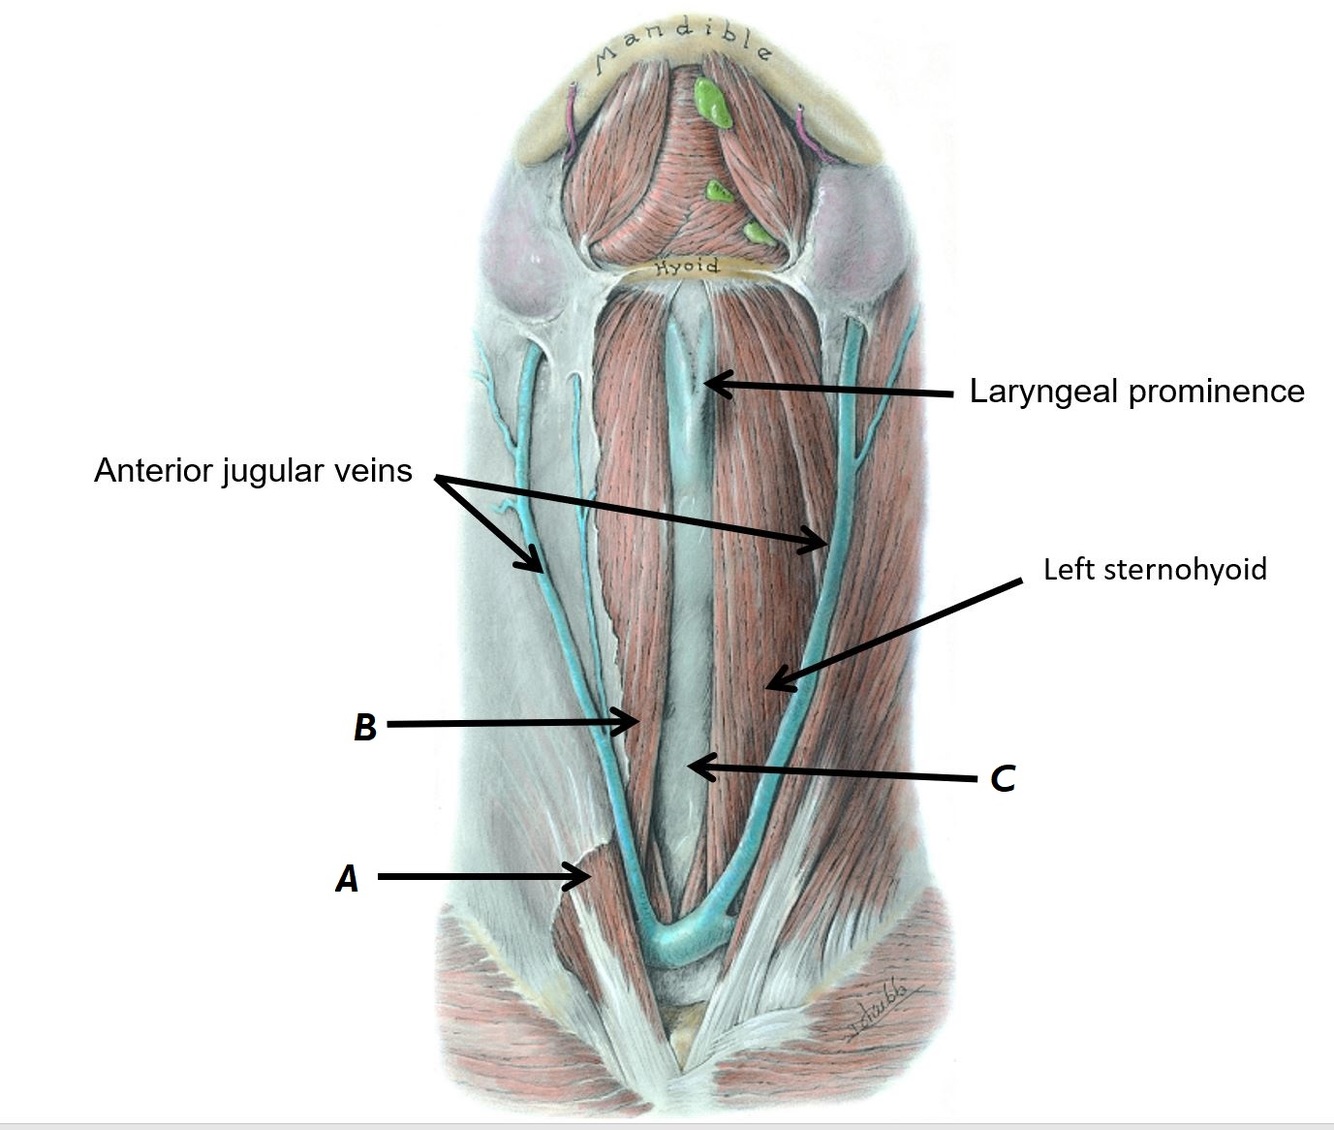

Name structures A and B

A - Anterior jugular veins

B - Left sternohyoid muscle